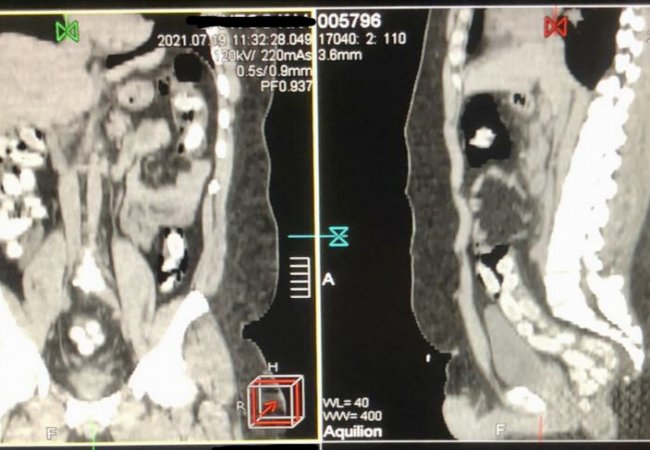

Маючи попередню оперативну інформацію, митники застосували щодо 29-річного чоловіка особистий огляд із залученням медичного працівника. Процедура відбувалася у медичному закладі із застосуванням комп’ютерної томографії черевної порожнини чоловіка.

Наркокур’єр виявився класичним «ковтачем», який перевозить наркотики в герметичних капсулах, використовуючи для цього власний шлунок.

Вилучення 90 капсул овальної форми, які знаходилися в його кішківнику, відбувалось медикаментозним шляхом і тривало майже три години поспіль. Вага брутто виявленого - 965 г. Згідно з експресаналізатором виявлене є кокаїном.